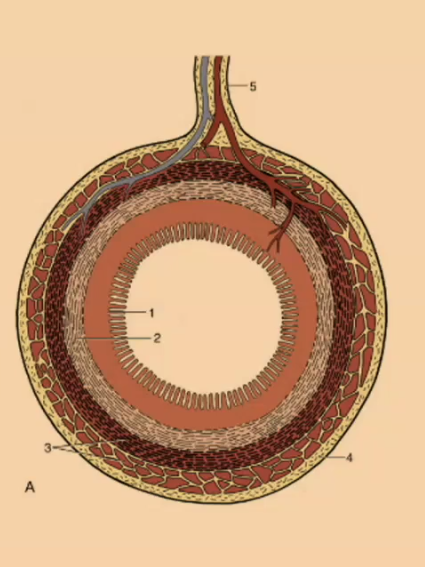

What is the outermost layer of the simple stomach?

Serosa

Serosa

What creates the mucosal folds in the simple stomach?

submucosa

What is the thinnest layer of the simple stomach wall?

Muscularis mucosa

What is the innermost layer of the simple stomach wall?

Mucosa

#1

Mucosa

#2

Submucosa

#3

Muscular (2 Layers)

#4

Serosa